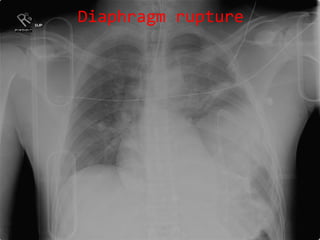

Diaphragm rupture